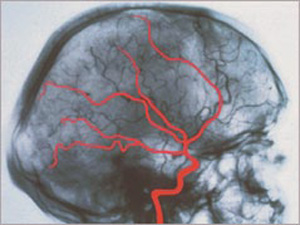

Egy halott agy röntgenképe

(Forrás: Deutsche Stiftung Organtransplantation, Neu-Isenburg

"Der Hirntod als der Tod des Menschen", Schlake/Roosen, Második kiadás, 2001)